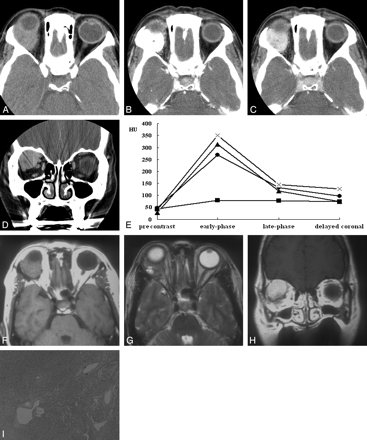

A–I, Case 2. Solitary fibrous tumor of the orbit in a 50-year-old woman. Axial precontrast (A), early-phase (B), late-phase (C), and delayed coronal (D) CT scans show a 30-mm well-defined soft tissue mass in the superolateral aspect of the right orbit near the lacrimal gland fossa. Compared with the cerebral gray matter, the mass is slightly hyperattenuated on precontrast CT scan (A). Marked homogeneous enhancement is seen on early-phase CT scan (B), and there is rapid washout of contrast material on late-phase (C) and delayed coronal (D) CT scans. The mass abuts and conforms to the posterior wall of the eyeball without causing significant indentation. E, Time-attenuation curve also reveals rapid enhancement and early washout of contrast material within the tumor (•), which is very similar to those of the internal carotid artery (×). ▴ = internal jugular vein. ▪ = medial rectus muscle. F–H, Compared with the cerebral gray matter, the mass is isointense and mixed isointense and hyperintense on axial T1- (F) and T2-weighted (G) MR images, respectively. Marked homogeneous enhancement is seen on coronal postcontrast T1-weighted MR image (H). Note the small areas of bright signal intensity within the tumor on T2-weighted image (G). I, Photomicrograph shows that the tumor has a patternless histologic architecture with hyalinized collagen bundles and multiple dilated vessels (hematoxylin-eosin, original magnification ×40).

The CT and MR imaging features of 6 patients with orbital SFT are summarized in the Table. All lesions were found as a solitary, well-defined, ovoid mass, ranging in size from 18 to 30 mm (mean, 24 mm). Three lesions were located in the postseptal orbit (Figs 1, 2), 2 in the lacrimal sac, and 1 on the lower eyelid (Fig 3). Although 2 of the 3 postseptal orbital lesions were found in the extraconal space at the superolateral (Fig 1) and superomedial aspect of the orbit, respectively, the remaining lesion was located in the intraconal space at the inferomedial aspect of the orbit (Fig 2). Although the eyeball was displaced by the lesion in all 3 cases, true indentation of the eyeball by the lesion was demonstrated in only 1 case. In no case was there a significant change of the bony orbit. In both lesions of the lacrimal sac, CT also showed smooth expansion of the proximal nasolacrimal duct by the inferior growth of the tumor. Compared with the cerebral cortex, the attenuation of the lesion seen on precontrast CT scans obtained in 5 patients was isoattenuated in 3 and slightly hyperattenuated in 2 (Fig 1A). There was no evidence of intralesional calcification demonstrated on precontrast CT scans. Compared with the cerebral cortex, all 3 lesions examined by MR imaging showed homogeneous isointense signal intensity on T1-weighted images (Figs 1F, 2B) and heterogeneous mixed isointense and hyperintense signal intensity on T2-weighted images (Figs 1G, 2C). In 1 of 3 lesions, signal-intensity void, tubular structures representing fast-flow vessels were found on T2-weighted and postcontrast T1-weighted MR images (Fig 2C–D).

On visual inspection, all 6 lesions showed marked homogeneous (n = 4) or heterogeneous (n = 2) enhancement on postcontrast CT and MR images (Figs 1B–H, 2A–D, 3A). In 3 patients examined with dual-phase CT, all lesions demonstrated rapid enhancement and early washout of contrast material (Figs 1, 3), and their time-attenuation curves revealed the very similar enhancing characteristics to those of the internal carotid artery (Fig 1E).

Enhancement of a certain tumor depends on various factors, including vascularity, capillary permeability, renal clearance, and composition of extracellular fluid. It can best be assessed radiologically by dynamic CT or MR imaging by evaluation of the chronologic changes of attenuation or signal intensity in the microcirculation of the tumor after injection of contrast material. Dual-phase helical CT can also be an alternative technique to dynamic CT for this purpose.28,29 With the addition of delayed coronal scans, it can demonstrate a rough approximation of enhancing characteristics of the tumor. In this study, all 3 lesions examined with dual-phase CT demonstrated rapid, intense enhancement at early-phase axial scanning, followed by significant progressive washout of contrast material at late-phase axial and delayed-phase coronal scanning. Furthermore, the time-attenuation curves of orbital SFT in our series were very similar to those of the internal carotid artery in both enhancement degree and shape of the curve (Fig 1E), which may be an additional clue to make the correct diagnosis.